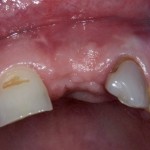

К сожалению, бывают ситуации, когда качественная имплантация просто невозможна из-за ряда факторов: недостаточный объем костной ткани, текущее ортодонтическое лечение и т. д.

В этом случае остеопластика делается отдельной процедурой. Ее принципы точно те же, но уже без импланта. Например:

Имплантировать в таких условиях — заведомо обрекать себя на хреновый, с точки зрения эстетики и функциональности, результат. Поэтому первым этапом проводим остеопластику. Объем небольшой, использовать в таких объемах костный блок не очень рационально. Воспользуемся аутокостной стружкой и мембраной.